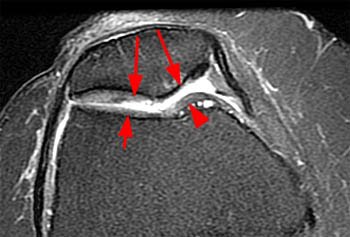

Хондромаляция 2 3 степень

Хондромаляция 2 3 степень 88 фото